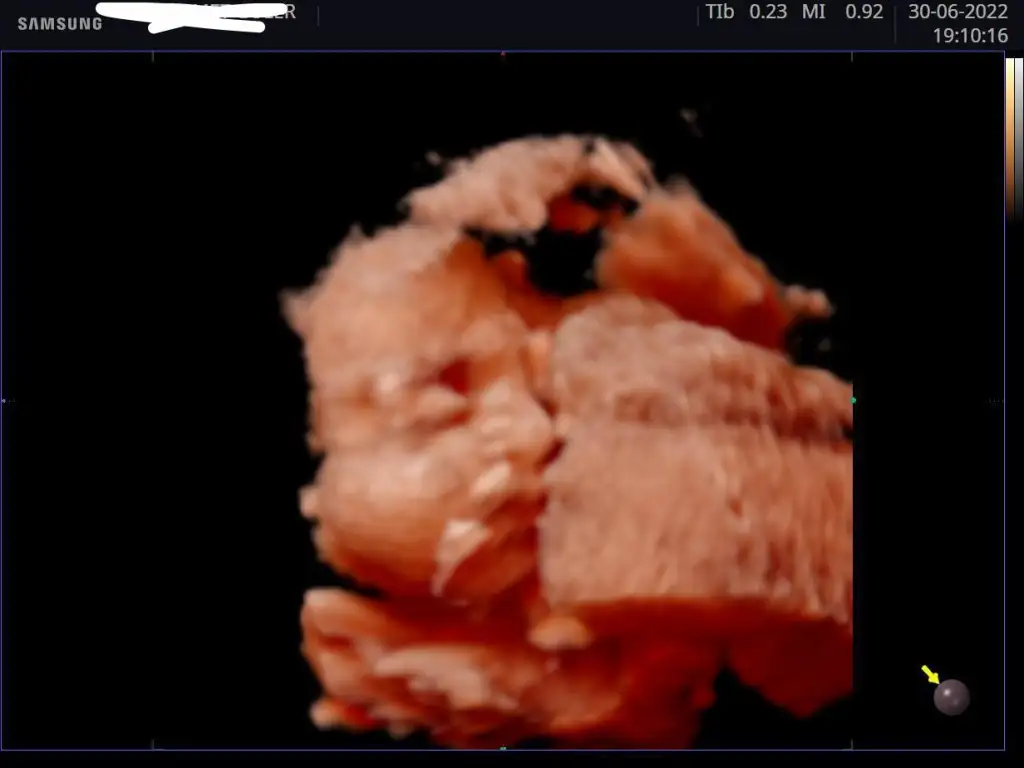

Kontrolümüz güzel geçti, şükür her şey yolunda 🙏🏻 1510 gr olmuşuz 29+5'teyiz. Yine yüzünü tam göstermedi minnoşum, plesantayı yastık gibi kullanıyoruz😬😅

Aynen bundan sonra hızlı kilo alımı başlıyormuş. Hep yan profil görebildik, buna da şükür☺️ Bı kaç isim var aklımda ama henüz babasıyla konuşmadım, o da son dakika golü yapmaya çalıştığımı düşünüyor ama ilgisi yok ben karar veremiyorum🙃

Benim de plesantam önde olduğu İçin çocuğun yüzünde sürekli plesanta ve kordon var😂

Buna da şükür, ağzı yüzü ne güzel belli.isim konusu başlı başına bir iş gerçekten, çocuğun ömür boyu ayrılmaz bir parçası olacak çünkü :)